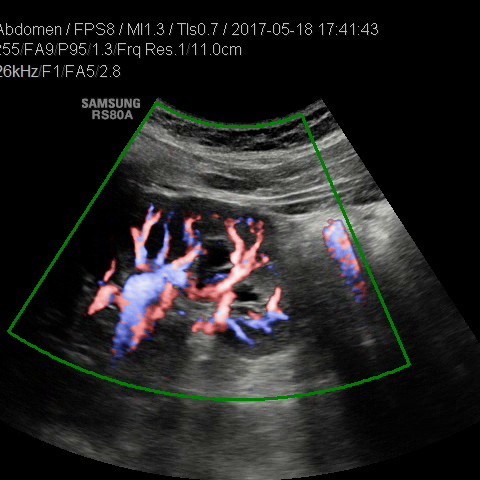

• USG jamy brzusznej

z oceną wątroby, trzustki, nerek, śledziony, pęcherza, gruczołu krokowego, dużych naczyń jamy brzusznej oraz przestrzeni okołoaortalnej.

• USG jamy brzusznej z oceną wątroby, trzustki, nerek, śledziony, pęcherza, gruczołu krokowego, dużych naczyń jamy brzusznej oraz przestrzeni okołoaortalnej

• USG doppler aorty i naczyń biodrowych

• USG doppler układu wrotnego

Rozszerzamy ofertę naszych pracowni: